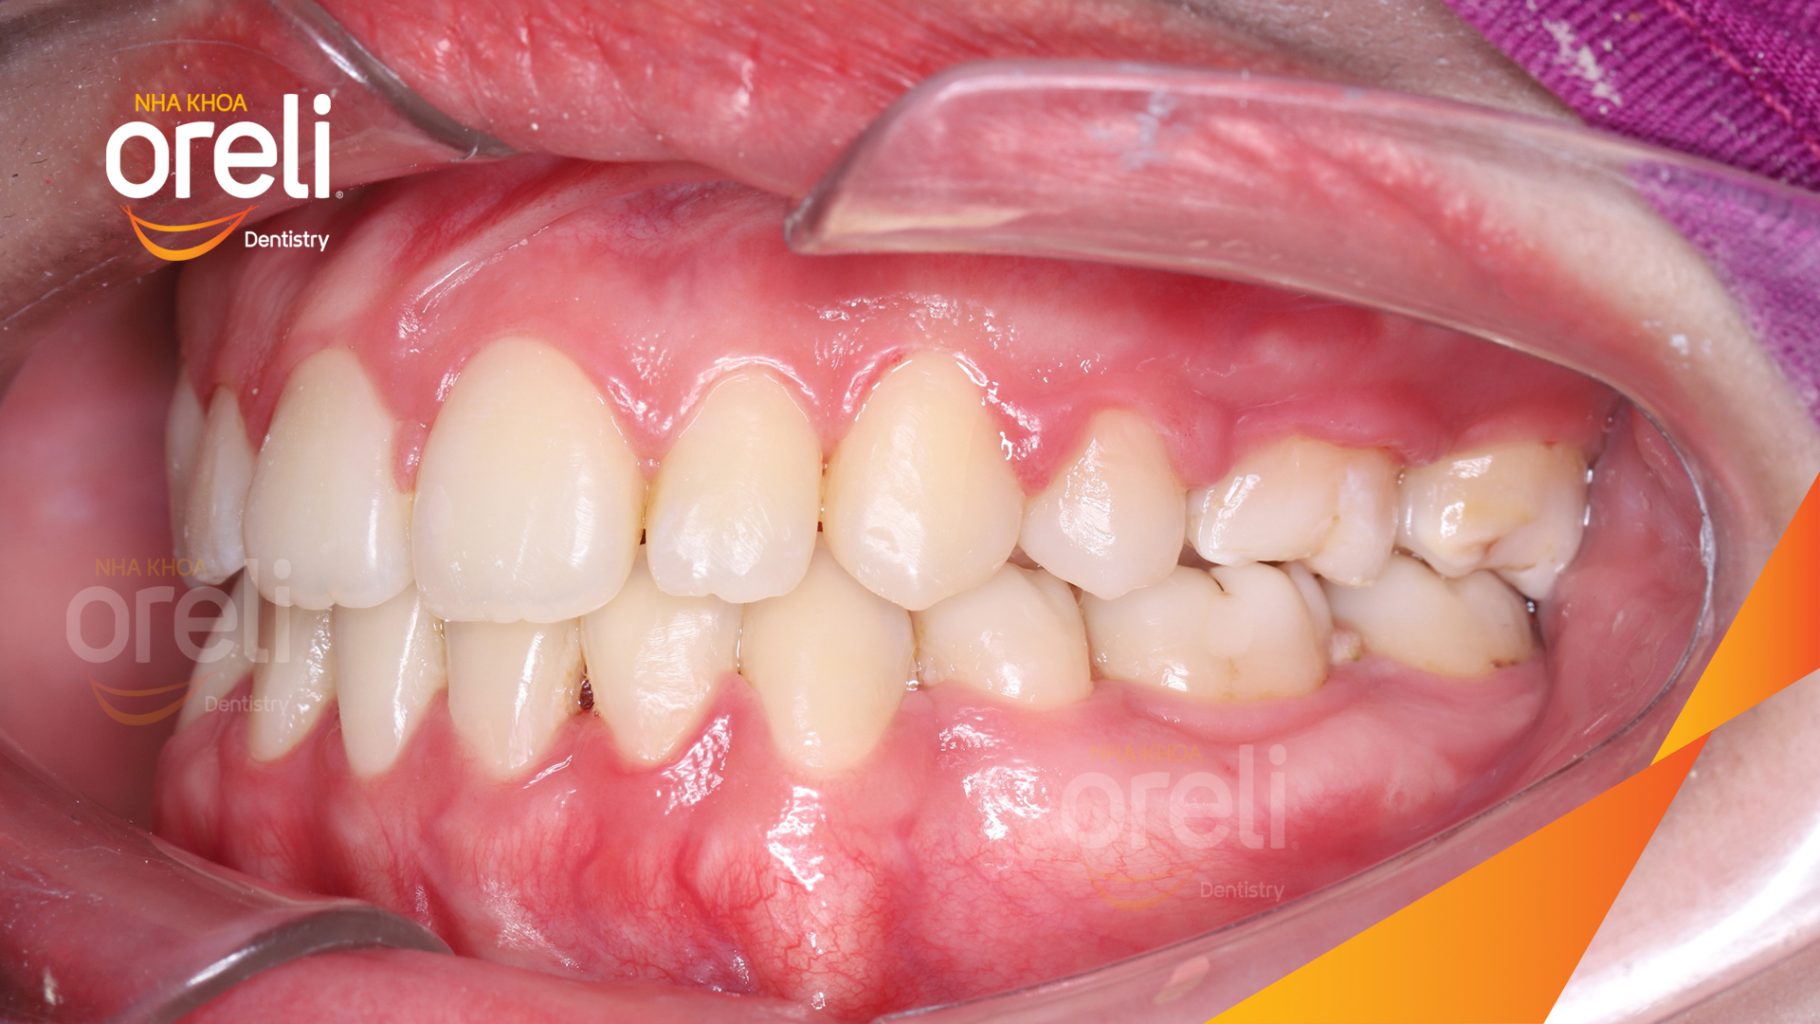

Hành trình thay đổi nụ cười ca lệch khớp cắn hạng 3, hàm dưới trượt ra trước và nhô xương hai hàm.

Hình ảnh thực tế